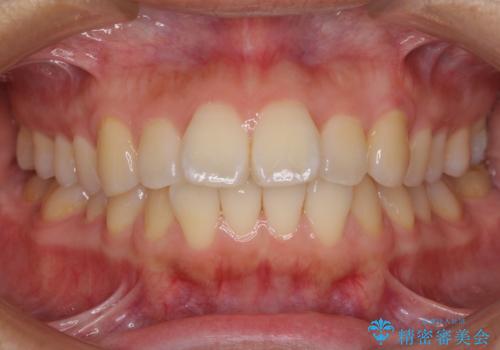

[ インビザライン矯正 ] マウスピースで治す前歯のがたつき

担当医 大元洋佑

![[ インビザライン矯正 ] マウスピースで治す前歯のがたつきの症例 治療前](https://seimitsushinbi.jp/wp/wp-content/uploads/2023/11/C7-500x350.jpg?v=1699665009)

![[ インビザライン矯正 ] マウスピースで治す前歯のがたつきの症例 治療後](https://seimitsushinbi.jp/wp/wp-content/uploads/2023/11/IMG_2993-500x350.jpg?v=1699664953)